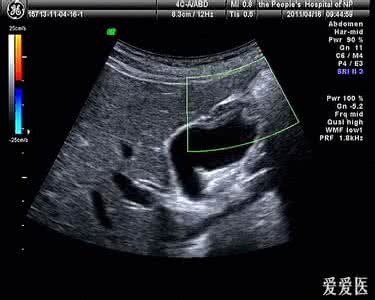

胆囊腺肌症的一种原因不明的良性增生性疾病。胆囊壁增生性疾病,女性更为常见。黏膜增生肥厚的病理变化,罗-阿窦数目增多、扩大成囊状,穿到肌层深,窦与胆囊腔连接到管道之间,形成假性憩室。

肌层明显增生,胆囊壁显著增厚,囊腔变窄。假性憩室中充满胆汁,可形成结石。分弥漫型、节段型和局限型三型。

整个胆囊壁均有增生。胆囊壁增厚,胆中造影时,造影剂可进入罗阿氏窦,可在增厚的胆囊壁内出现点状阴影。

增生的胆囊壁,常引起胆囊环形狭窄,狭窄,超过2mm壁厚,不规则的边缘。

胆囊壁局部发生明显增厚,常为单发,多位于胆囊底部,易被误为肿瘤,该型可分有内翻、外翻和中间位三种表现。